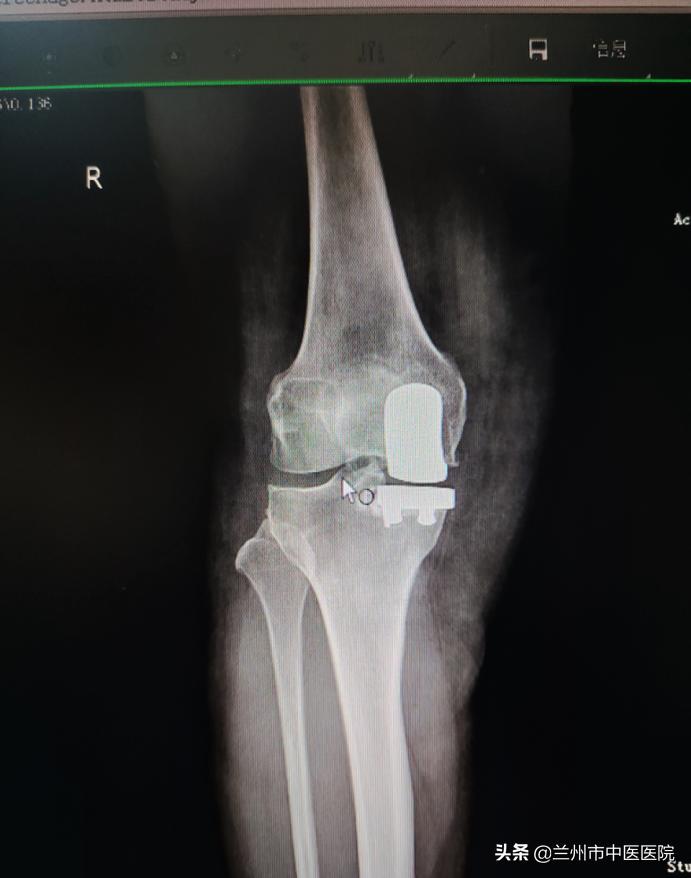

近日,兰州市中医医院骨科团队精诚合作,在麻醉科等相关科室的全力配合下,成功完成了单间室膝关节骨性关节炎、单髁置换术,手术顺利完成,病人术后恢复良好,家属满意。

膝关节的单髁置换手术,仅把膝关节的单侧髁部置换为表面假体。把膝关节由前正中线上等分,单侧髁部就是内侧或者是外侧的部分。简单来说,就是对一半膝关节进行置换,这一半膝关节主要构成是胫骨髁和股骨髁。当患者膝关节因骨性关节炎等发生了的严重病灶,但病变范围比较局限,该手术可以保留2/3正常的膝关节结构,让患者可以保留关节自然本体的感觉,恢复关节的活动,还可以延缓患者做全膝关节置换的时间。

单髁置换术具有手术创伤小、术后恢复快、病人疼痛轻、失血少、术后本体感觉好、花费少等特点。用于膝关节早期病变,可明显改善病人生活质量,延缓病人的全膝置换时间,对很多患者来说可以免除全膝关节置换。

单髁置换术特点:相对于全膝关节置换术,单髁置换术具有以下特点:创伤小。手术切口大约只有传统全膝关节置换手术的一半,切除置换的骨与软骨组织不到传统手术的三分之一;疼痛轻。术后疼痛较轻,在规范的镇痛方案辅助下,多数患者几乎感觉不到疼痛;恢复快。大多数患者术后当天即可下床活动并完成日常生活,一个月以内基本恢复正常状态;更接近正常的生理活动。由于保留了膝关节的正常结构,接受这类保膝手术的患者术后膝关节能够完成膝关节旋转、极度屈曲、深蹲等动作。